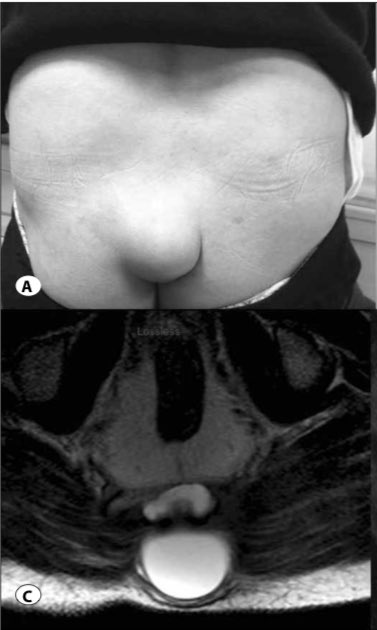

الذيل البشري: هو مصطلح لوصف (نتوءات مغطاة بالجلد) في المنطقة القطنية العجزية والعصعصية من الظهر، ويكون شكلها مشابه لذيول الحيوانات

وصولاً للعام 1984 في دراسة تم فحص 33 حالة وتصنيف الذيول فيها الى نوعين:

1. ذيول حقيقية: وصفوها بقايا ذيل الجنين علماً انها تفتقر للعظم والغضاريف والحبل الشوكي

2. ذيول كاذبة: وصفوها بتشوه (استطالة شاذة) في الفقرة العصعصية

وصولاً للعام 2005 مع تقدم العلم وتقنيات التصوير المقطعي والإشعاعي

تم تحديد الأهمية المرضية وحالات التشوه الشاذة المرتبطة بالعمود الفقري مع العمل على صياغة استئصال جراحي

وتبيان السبب بكونه اضطراب في الأعصاب الثانوية و/أو انحسار في برعم طرف الجنين